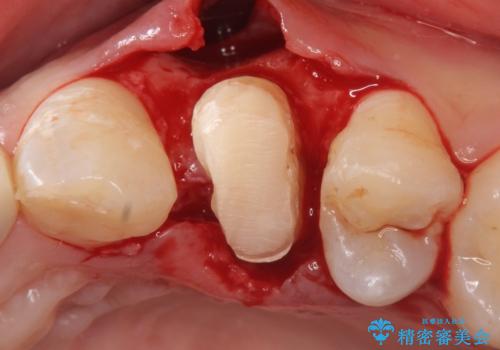

挺出終了後は歯肉切除および骨外科により歯周組織を整え、オールセラミッククラウンによる補綴を行いました。

虫歯が進み歯茎より深くなってしまうと、虫歯を取り残してしまうリスク、樹脂の硬化の妨げ、補綴物の不適合、歯肉炎・歯周病のリスクの増大等様々な弊害が起こり得ます。

そのため当院では歯周外科手術(歯茎を下げる手術)や歯の挺出による、虫歯が歯茎より深いという問題の解決を推奨しております。